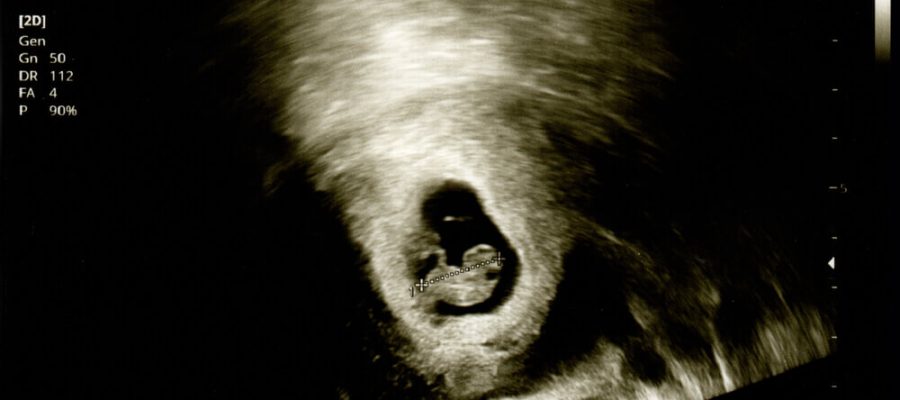

Rahim filmi, temel olarak ele alınan rahim boşluğunun ve tüplerin görüntülenebilmesi için kullanılan görüntüleme tekniğidir. Rahimde görülen rahatsızlıkların doktor tarafından kesin olarak teşhis edilebilmesi için bu görüntüleme metodundan yardım alınır. Görüntüleme metotlarına göre rahim filmi fiyatları değişebilir.

Rahimdeki şekil bozukluğu, miyop, polip benzeri kitleler ve yapışıklıklar, rahim tüplerin şişmesi veya tıkanması üzerine bazı anormallikler görülür. Bu durumun fiziki muayene sonucunda kesin olarak tespit edilmesi mümkün değildir. Fakat yapılan rahim filmi ile birlikte teşhis koyulabilir.

Burada yer alan rahim tüpleri ile rahim boşluğunun görünebilir olması için film çekiminden önce hastaya kontrast maddesi verilir. Bu madde sayesinde daha net ve detaylı görüntüler elde edilebilir.

İşlem yapılmadan önce hastaya kontrast maddesi verilir. Bu madde sayesinde detaylı görüntüleme gerçekleştirilir. Radyolojik olarak tercih edilen HSG filminin jinekologlar tarafından yapılması büyük önem arz eder.